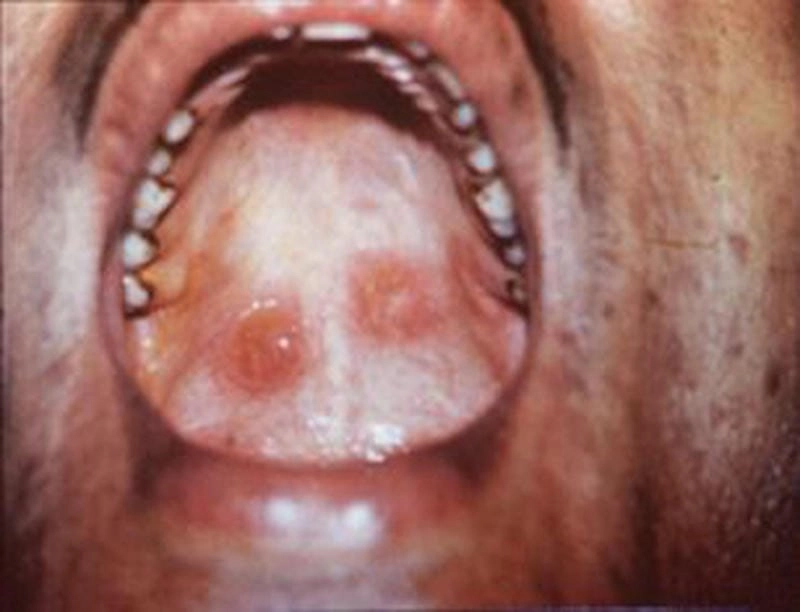

Nhiều người vẫn mơ hồ không biết hình ảnh bệnh giang mai là như thế nào, và đó chính là lý do họ dễ lơ là cảnh báo đầu tiên. Những vết trợt nông không đau, không ngứa, tưởng chừng vô hại nhưng lại chính là “báo hiệu đỏ” cho một chuỗi biến chứng nguy hiểm. Dưới lớp da tưởng như lành lặn kia có thể là ổ chứa xoắn khuẩn giang mai đang âm thầm tấn công hệ thần kinh, tim mạch.

Nếu bạn nghĩ giang mai là căn bệnh đã “xưa như trái đất” thì hãy xem ngay tổng hợp ảnh giang mai mới nhất 2025. Những hình ảnh cận cảnh, rõ nét từng giai đoạn từ sơ cấp, thứ cấp cho đến tiềm ẩn và cuối cùng là giang mai thần kinh sẽ khiến bạn “rùng mình”. Đây không chỉ là tài liệu y khoa mà còn là lời cảnh báo nghiêm túc cho những ai đang sống buông thả và thiếu kiến thức phòng bệnh.

Qua những hình ảnh bệnh giang mai được chia sẻ, bạn có thể nhận diện sớm các dấu hiệu bất thường. Việc phát hiện sớm và điều trị kịp thời giúp hạn chế biến chứng nguy hiểm, bảo vệ sức khỏe bản thân và cộng đồng.